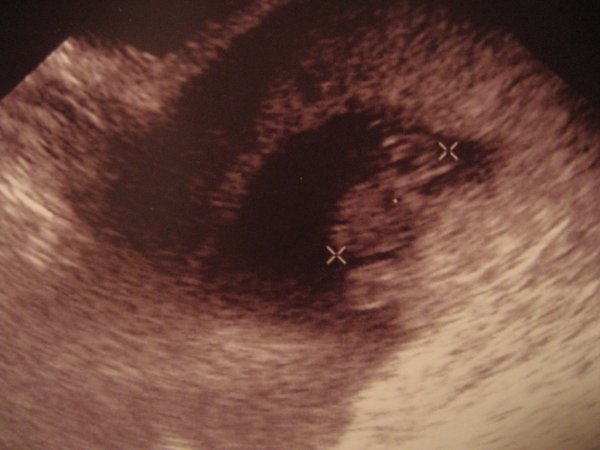

Rólam: hétvégén nagyon rosszul voltam, nagyon el kezdett görcsölni a hasam. Mivel az előző terhességet is ebben az időben veszítettem el, meg voltam győződve róla, hogy kész, nekem ennyi jutott megint a kismamaságból. Mára azért egy kicsit jobb lett, de azért elmentem a dokimhoz. Megvizsgált, teljesen zárt a méhszáj. Csinált egy uh-t, hogy a babóval mi van: már 19 mm-es, tehát szépen növöget, és változatlanul ver a kicsi szíve! Látszik a méhlepény, látszik még a szikhólyag is, azt mondta, hogy az is nagyon jó jel. Szóval vetélésnek semmi jele! :lol: Hogy mi ez a hasgörcs? Ja, hát azt nem tudjuk! :roll: :twisted: Most szednem kell ipari mennyiségben a Magne-B6-ot, hátha jobb lesz. Ja táppénz így tuti a 12. hétig, szó sem lehet róla, hogy visszamenjek november elején dolgozni. :roll:

Azért felteszem az új képet a babámról.

Biztos nem lesz semmi gond, pihenj sokat!Én ha újra babás leszek, nem fogok dolgozni, az első hónapokban biztos nem...Az UH képen a két X mit mutat?

Luca! Az egyik X a popsija, a másik a feje búbja. Hogy melyik melyik én sem tudom. :oops: Az orvos állítólag látta a két kis kezét is, de nekem azt már végkép nem sikerült kivennem. :oops: Következő uh már csak a 12. héten lesz, akkor már igazi baba formája lesz. :lol: